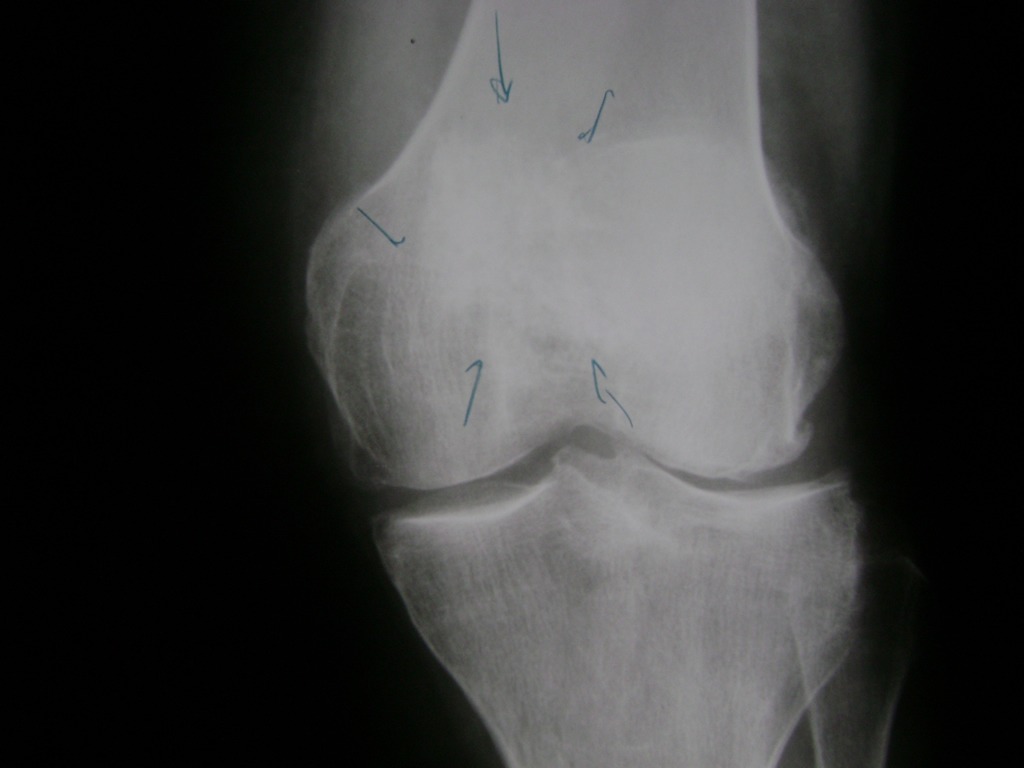

Cirugía de Fémur - Rodilla